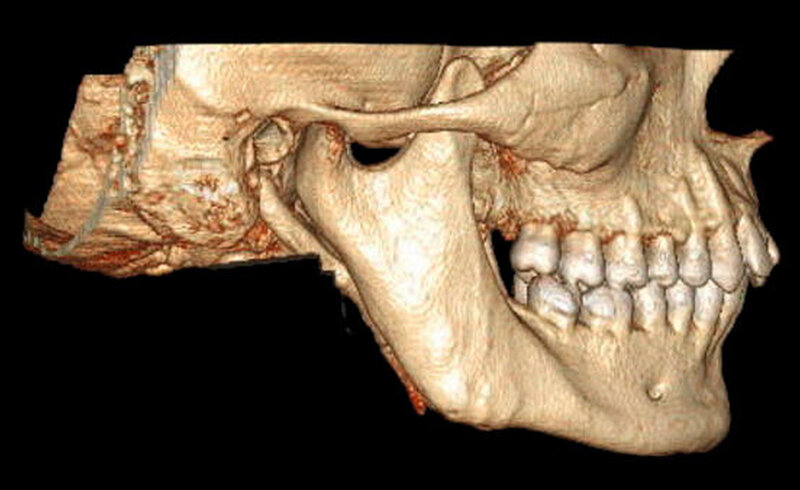

In der erweiterten radiologischen Diagnostik mittels CT zeigten sich symmetrisch angelegte Kiefergelenke beidseits ohne arthrotische Veränderungen oder signifikante Deformierungen. Ein Hinweis auf Luxation ergab sich nicht. In den axialen Schichten stellten sich beide Proc. coronoidei bis hoch in die jeweilige Fossa temporalis dar. In der 3-D-Rekonstruktion imponierten die hyperplastischen Proc. coronoidei beidseits. Diese ragten weit über die Jochbögen hinaus und schränkten dadurch die Mundöffnung ein (Abbildung 3).